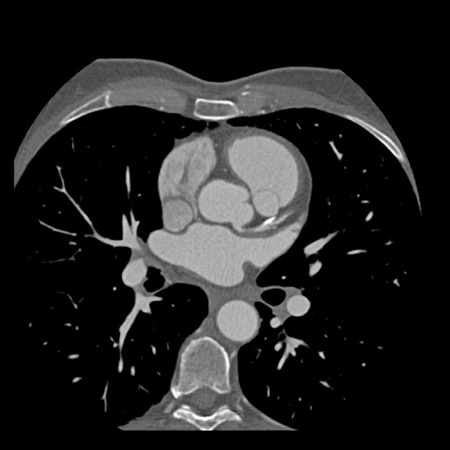

case 5 – CTA overestimates stenosis due to calcium

First, scroll through the CTA images.

How would you describe the findings on the coronary CTA?

Continue with the curved MPR images of the same patient.

The findings are:

- Long, partially

calcified plaque in the LM-LAD causing moderate stenosis (50-69%) (white

arrows).

This segment of the LAD is difficult to evaluate because of blooming and step